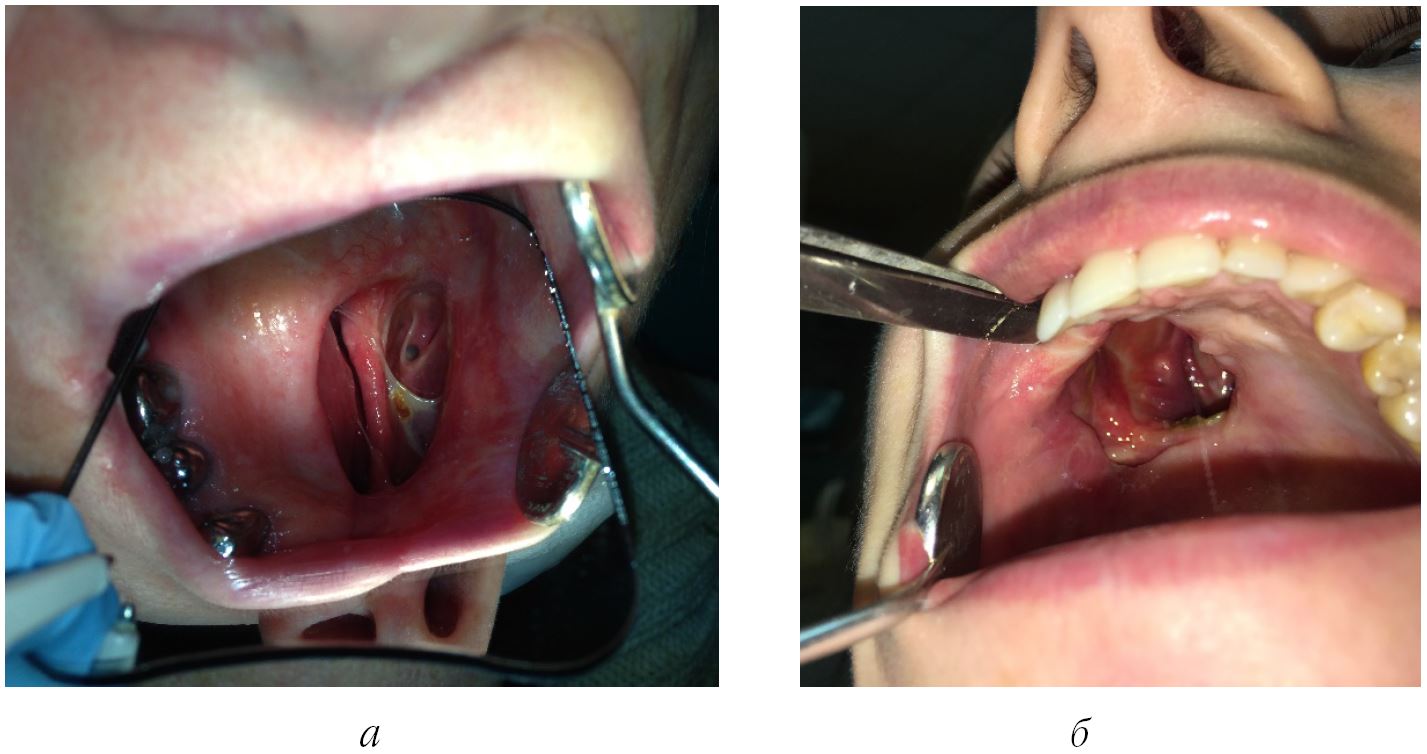

Профилактика и лечение онкологических заболеваний у населения многих стран мира сохраняет свою актуальность как сложнейшая, до конца не решенная задача медико-социальной значимости. По данным Международного агентства по изучению рака (International Agency for Research on Cancer, IARC; WHO), в мире ежегодно регистрируется более 12 млн новых случаев рака и более 6 млн смертей от него. У населения Российской Федерации ежегодно фиксируют до 450 тыс. новых случаев злокачественных опухолей, около 25 % которых локализовано в челюстно-лицевой области. Последнее актуализирует поиск решений многочисленных лечебно-диагностических проблем современной онкостоматологии, начиная с задач формирования высокого уровня онкологической настороженности, ранней диагностики и скрининга потенциально злокачественных заболеваний полости рта и заканчивая полноценной стоматологической ортопедической эстетико-функциональной реабилитацией пациентов с приобретенными (послеоперационными) дефектами челюстных костей [1–4]. Медицинская стоматологическая и социальная реабилитация пациентов с дефектами верхней челюсти, особенно при наличии сообщения с полостью носа или верхнечелюстным синусом, требует применения сложных съемных протезов с опорой на сохраненные участки челюсти и имеющих обтурирующую часть для создания достаточного герметизма между полостью рта и носа (рис. 1). Как правило, в подобных случаях протез-обтуратор имеет расширенные границы и, как следствие, больший вес, что ухудшает фиксацию и стабилизацию конструкции, приводит к перегрузке оставшихся зубов [5]. В связи с этим при конструировании зубочелюстных протезов представляется обоснованным сделать акцент на применении более легких, функциональных и эстетичных конструкционных материалов с достаточными параметрами прочности. Успешное решение этой задачи на основе биомеханического моделирования – залог полноценной ортопедической стоматологической реабилитации пациента с приобретенными дефектами ЧЛО, достижения желаемого структурно-функционального и эстетического результата.

Рис. 1. Клинические случаи: а – пациентка М., 65 лет: пострезекционное ороназальное сообщение слева (вид через зеркало); б – пациентка К., 27 лет: пострезекционное ороназальное сообщение справа